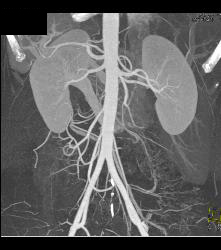

Trauma to Right Axillary Artery With Pseudoaneurysm